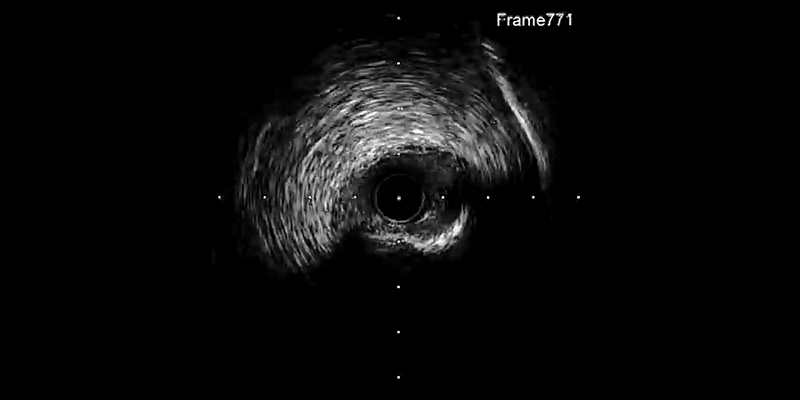

• IVUS (OptiCrossTM IVUS catheter) showed plaque rupture after rotablation at different levels. However, a calcium ring of more than 270º was observed at the site of maximum plaque.

• For this reason, plaque modification was completed with a 2.5x6mm FlextomeTM Cutting BalloonTM.

IVUS AND CUTTING BALLOON™

• IVUS is an essential tool in conjunction with rotablation. Not only to evaluate the size of the artery and plaque characteristics, but also to identify the need to complete the procedure with a non-compliant balloon or with a cutting balloon if the ring of calcium is still present.

• The Flextome™ Cutting Balloon™ Device was successfully used after rotablation prior to stenting to enhance the vessel preparation. The precise cutting action of Flextome™ Cutting Balloon™ changed the lesion compliance, enabling uniform stent expansion that will lead to a good long-term result after DES implantation